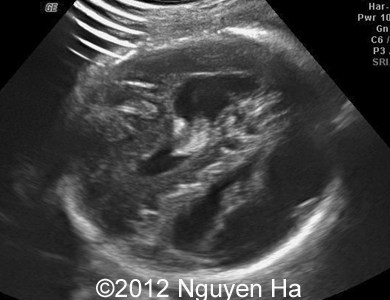

Figure 8-15: 4 days later; image 1-4 suggesting a middle cerebral artery infarction with formation of schizencephaly, no more cortex at the level of the insula.

A 30-year-old woman (G1P0), with unremarkable family history, presented to our unit at 36 weeks of her pregnancy. She did not undergo any previous screening tests. Our examination revealed unilateral hypoechoic inhomogeneous mass within cerebral parenchyma. Our initial diagnosis was teratoma, but repeated exam after four days showed structural changes and different echogenicity of the mass and so our final diagnosis was cerebral hemorrhage. The findings were confirmed by MRI scan.